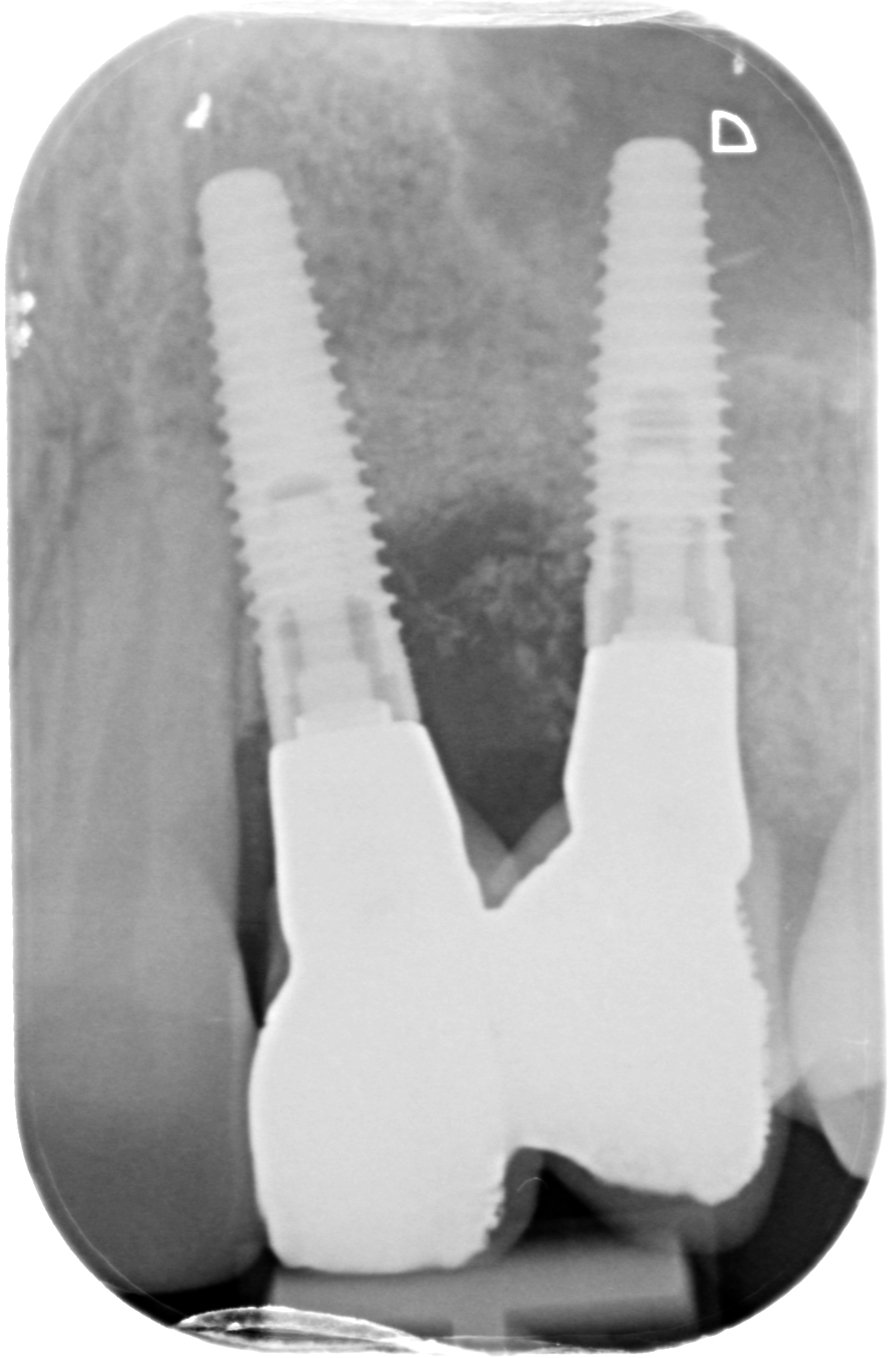

3D guided bone regeneration using an e-PTFE, Ti-reinforced NeoGen® membrane and 100% autogenous bone is a fully predictable treatment for the severe hard and soft tissue atrophy on the Aesthetic Zone. This statement is supported not only by panoramic and periapical x-rays, but also by CBCT sectional cuts where we can see the complete stability of the regenerated bone.